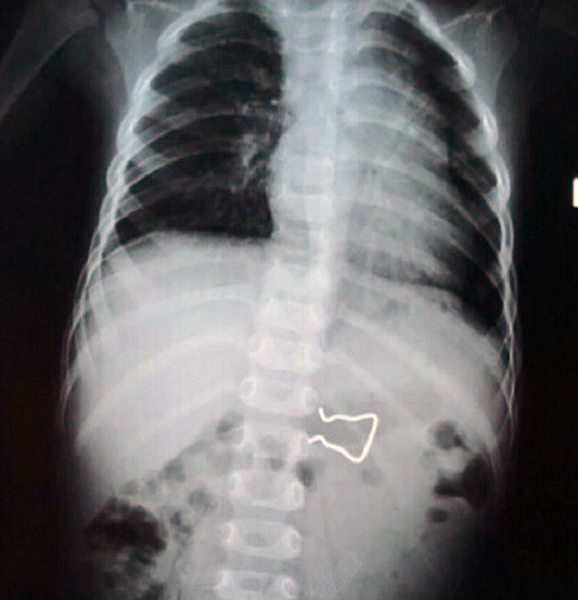

Tại đây, sau khi xem qua y bạ từ tuyến dưới cùng với thông tin do người thân bệnh nhi cung cấp, các bác sỹ đã tiến hành kiểm tra chụp X-quang khoang bụng bệnh nhi K. để xác định vị trí của chiếc móc. Hình ảnh X-quang cho thấy chiếc móc khóa sắc nhọn đang nằm trong đường tiêu hóa của bệnh nhi, nguy cơ gây thủng ruột nếu không được can thiệp sớm.